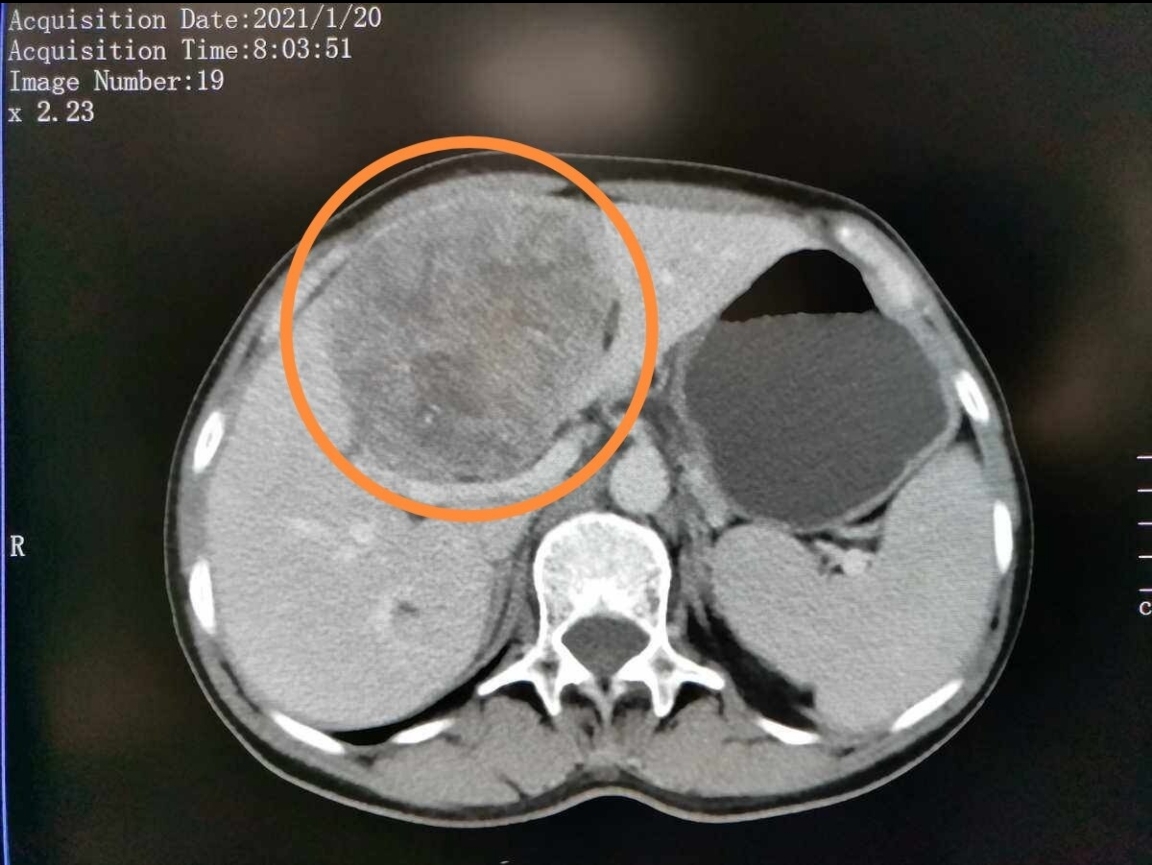

胰腺癌就診指南(9):一例胰體尾癌術后肝轉(zhuǎn)移的真實治療

患者,女,63歲,2023年6無明顯誘因出現(xiàn)腹部不適。2023.06.20到我院查CT顯示:胰腺頸體部腫塊,考慮MT,肝胃間隙及胰周小淋巴結(jié),肝腎多發(fā)囊腫。查CA19-9314;CA12532.7;CEA6.34。2023.06在全麻下行胰體尾切除+脾切除+門靜脈部分切除人工血管置換手術,術后病理:中分化導管腺癌,淋巴結(jié)(2/19)(轉(zhuǎn)移數(shù)/淋巴結(jié)總數(shù)),基因檢測發(fā)現(xiàn):KRASG12D突變。??術后復查:2023.07.24CA19-9?79.8U/ml術后輔助治療方案:AG;時間:2023.07.-2023.12;期間2023.10.11查?CA19-920.3、2023.12.13查CA19-919.3,降到正常。建議患者再維持治療一段時間,患者不愿意,遂在當?shù)仉S訪。2024.03.21復查?CA19-9:263????CA125110????CEA13,腫瘤標志物反彈。2024.03.21增強CT提示:?后腹膜軟組織致密,肝轉(zhuǎn)移可能2024.03.29PET-CT:腸系膜根部軟組織致密影與術區(qū)分界不清,F(xiàn)DG高代謝,考慮復發(fā)可能;肝左葉M;腹膜后淋巴結(jié)M可能。??患者自行在外院行二線治療方案:NALIRIFOX,療程:2024.04-2024.06療效:2024.06CA19-9?3000+;同期CT:評估PD,肝轉(zhuǎn)移灶進展后患者又在外院改行三線治療方案:卡度尼利單抗+戈沙妥珠單抗,療程:2024.07-2024.09療效:2024.09CA19-9?5000+;同期CT:較2024.07.31相比,術區(qū)復發(fā)同前,肝M較前進展。評估患者PD。患者又來我院尋求治療方案,入組我院的臨床研究,方案:KRASG12D抑制劑+ADC;定期復查腫瘤標志物,影像評估為PR。??最后總結(jié)下整個治療過程中腫瘤標志物CA19-9等的變化,目前病情穩(wěn)定。